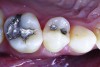

Figure 7. The occlusal outline was extended only to include carious enamel, provide access to the carious dentin, and remove any residual amalgam staining.

Figure 7